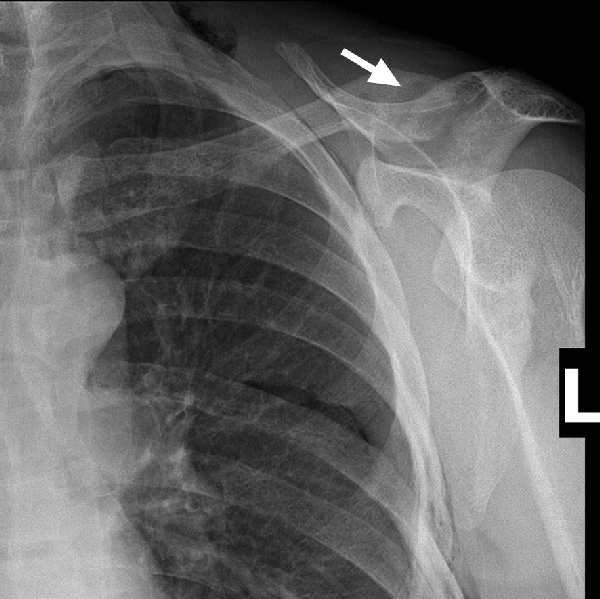

A 45-year-old man with no significant past medical history presented with a fractured clavicle and evidence of a radiolucent lesion (brown tumour) within the clavicle on x-ray, characteristic for hyperparathyroidism (Box 1). On further investigation, biochemical analysis showing raised serum calcium and parathyroid hormone (PTH) levels confirmed primary hyperparathyroidism. A thyroid ultrasound showed a 39 × 29 × 32 mm mass in the right lobe, suggestive of a tumour. A staging computed tomography (CT) scan of the neck and chest and a bone scan showed bone changes consistent with hyperparathyroidism throughout the axial and appendicular skeleton. There was no evidence of metastatic disease.